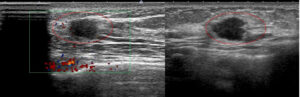

線維腺腫っぽく見えても癌 case.3

これなんかも(左)癌なのだから、やはり「なのは」さんの所見を「線維腺腫だ!間違いない」などというのが如何に無知なことか!

典型的な「線維腺腫(実際に生検で線維腺腫と確認)」と典型的な癌「私のcat.7」を提示します。

左と右、どちらが線維腺腫でどちらが癌なのか?当ててください(皆さんなら簡単ですね? 引っかけはありません)

このくらい典型(私cat. 2)ならば画像だけで「線維腺腫で大丈夫です」と言えるのです。

♯逆にこれくらい典型(私cat. 7)ならば画像だけで癌と言い切ってもいいでしょう。